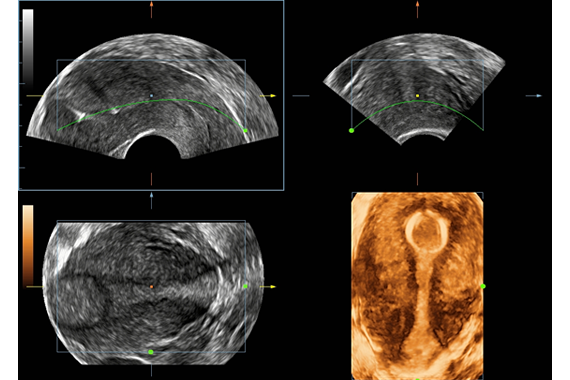

Smart Planes CNS Программное обеспечение для автоматического получения стандартных срезов головки плода из объемного изображения